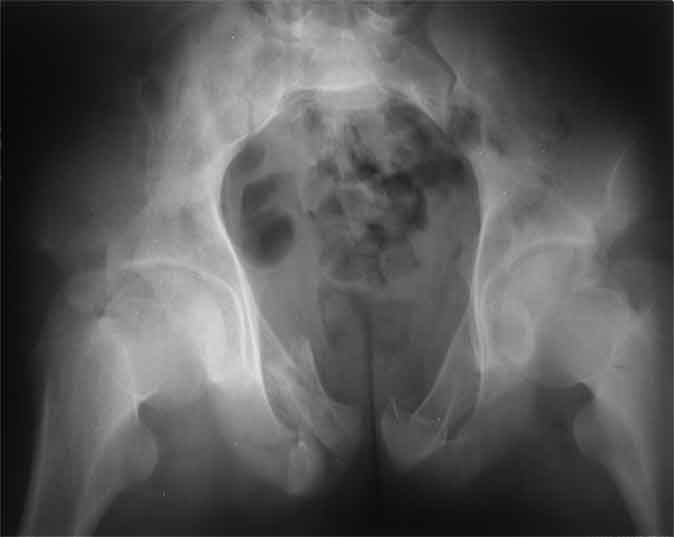

А чего там собственно таинственного? Билатеральное ротационно-нестабильное повреждение таза, перелом крестца в I зоне (по Denis)справа,частичное повреждение левого КПС, оскольчатые переломы лонной, седалищной костей справа (В3.2). Повреждение достаточно стабильное + молодой возраст+ сроки - оперативного лечения не требует.

Не смог разглядеть на представленных картинках частичное повреждение левого КП, повреждение Денис1-2 справа? 3Д реконструкции в инлет и боковой проекциях убедительно не демонстрируют типа повреждения задних отделов тазового кольца(справа боковая масса скомпремирована), Наверное, у тебя есть возможность оценить тип перелома крестца по прямой проекции 3Д.

По поводу классификации повреждения тазового кольца( по тем данным . что видны на представленных картинках):

по Pennal et al.- латеральное компрессионное повреждение тип В(ротационно-нестабильное (внутренняя ротация), вертикально стабильное)

по Tile classif. тип В2-1 - частично стабильное повреждение с неполным разрывом задней дуги.

По вертлуге- смог разглядеть только изолированный перелом передней колонны.

Насколько я понял из твоего письма, обращенного к анонимному vit, ты не видишь показаний к реконструкции перелома. Я бы взялся за реконструкцию(илео-ингвинальный доступ), хоть прошел и месяц после травмы: боковая 3Д показывает смещение нагрузочной зоны впадины, что однозначно будет способствовать разрушению хряща головки и впадины( особенно у 16 летнего пациента с ожидаемым высоким уровнем активности) + изменение геометрии впадины за счет неустраненного смещения фрагментов колонны (КТ, 3Д данные).

На мой взгляд, без реконструкции этот сустав обречен (концепция вторичной конгруэтности в данных условиях работать не будет), реконструкция дает шанс на восстановление функции сустава.

В данном случае 3D и корональные срезы КТ менее информативны, чем поперечные. Согласен с левосторенним минимальным повреждением КПС, но не смог уловить перелом крестца.

По представленным материалам, мне кажется, перелом был передней колонны ацетабулум с минимальным вовлечением нагрузочной поверхности сустава, левосторенний повреждение КПС и лонных костей.